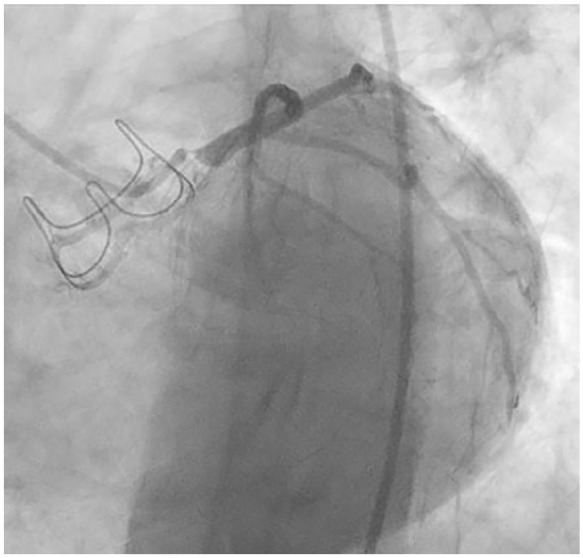

Iatrogenic coronary artery obstruction is one of many life-threatening complications associated with aortic valve replacement. Although very few cases of ostial coronary artery occlusion following cardiac surgery are reported, the consequences can be catastrophic due to increased risk of mortality. Due to the rarity, prompt investigation and early management are crucial to manage this catastrophic sequelae. We report a case in which a 61-year-old female presented with acute coronary syndrome 4 months after surgical aortic valve replacement and was found to have 99% left main ostial coronary artery occlusion.